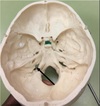

1. What is the name giving to this structure? 2. What structures are present in the lateral grooves of this structure?

1. Skull Cap or Calvaria 2. Middle Meningeal Vessels

1. What is the name giving to this structure?

Superior Saggital Sinus

1. Identify the spaces labelled.

Anterior Cranial Fossa, Middle Cranial Fossa, Posterior Cranial Fossa

1. Identify the elevation. 2. What is the function of this structure?

1. Frontal Crest and Crista Galli 2. Attachment of Falx Cerebri, olfactory bulbs run lateral to it.

1. Foramen caecum 2. it transmits the emissary vein from the nose to the superior sagittal sinus. This has clinical importance in that infections of the nose and nearby areas can be transmitted to the meninges and brain from what is known as the danger triangle of the face.

1. Identify the elevation. 2. What is the function of this structure? 3. What structures are immediately lateral to this elevation? 4. This structure is perforated by what structures?

1. Crista Galli 2. Attachment of falx cerebri 3. Olfactory bulbs 4. Olfactory nerve rootlets

1. Identify the depression. 2. What structure is traversed through this depression if it is patent? 3. The structure identified in 2. connects which two areas? 4. When this structure is clinical significance if this structure is patent?

1. Foramen caecum 2. Emissary veins 3. Nose to superior saggital sinus 4. Infection can spread; meningitis

1. Identify the structures.

ORBITAL PLATES of Anterior Cranial Fossa

1. Identify the structure.

Dorsum of sellae pituitary gland rests here. Macroadenoma of pituitary will be seen as deviation of this in X-Ray

1. Identify the structure. 2. Name the structures passing through it

1. Optic canal 2. Optic nerve and opthalmic artery

1. Identify the structure. 2. What structure islodged here?

Hypophysial Fossa Pituitary Gland

1. Identify the structure. 2. What structure is lodged here?

1. Internal occipital crest 2. Falx cerebri attachment

1. Identify the structure. 2. What structures traverse this canal

1. Foramen Rotundum 2. Maxilliary nerve, V2 off trigeminal M.R Triangle R.O.S.L

1. Identify the structure. 2. What structure traverses this canal?

1. Superior Orbital Fissure 2. CN3,4,5 V1 off trigeminal, opthalmic artery

1. Foramen Spinosum 2. Middle Meningeal Artery, Meningeal branch of Mandibular Nerve Foramen Ovale (red arrow) Accessory Meningeal Artery, v3 c5 Mandibular Nerve, Lesser Superficial Vitrosal nerve, Emissiary nerve

1. Foramen Lacerum 2. The artery of pterygoid canal, the nerve of pterygoid canal. Internal carotid runs superiorly not through.

1. Identify the structure. 2. What produces this structure?

1. Petrous Crest 2. Sphenoid and occipital bones Arcuate Eminence due to Superior Semicircular Canal.

1. Identify the structure. 2. What structures traverse this canal?

1. Internal Acoustic Meatus 2. transmits the vestibulocochlear nerve, the facial nerve, and the labyrinthine artery (an internal auditory branch of the basilar artery). It also contains the vestibular ganglion. CN 7 & 8

1. Identify the structure. 2. What are the subdivisions of this structure? 3. What structures traverse these subdivisions?

1. Jugular Foramen, CN 9,10, 11 2. Anterior Intermediate, posterior 3. The anterior compartment transmits the inferior petrosal sinus and glossopharyngeal nerve (CN IX) The intermediate transmits the vagus and accessory nerves (aka cranial nerves number X, and XI respectively). The posterior transmits the sigmoid sinus (becoming the internal jugular vein) and some meningeal branches from the occipital and ascending pharyngeal arteries.

1. Identify the canal. 2. What structures traverse this canal?

1. Hypoglossal canal 2. Hypoglossal Nerve

1. Formaen Magnum 2. Spinal cord, CN11 accessory, vertebral arteries.